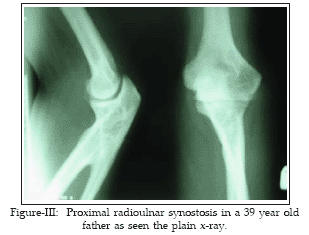

A 5-year-old daughter with right proximal radioulnar synostosis visited our clinic. She was the second child of the family. The older child did not suffer radioulnar synostosis. Her 39 year old father had suffered proximal bilateral radioulnar synostosis. Thirty years ago, when he was nine year old he visited a hospital because of limitations in supinations and fixed pronations of the two radioulnar joint. After physical and radiological examinations bilateral radioulnar synostosis was diagnosed. Surgery was recommended immediately which could not be performed due to some problems. In the physical and laboratory examination, no other anomaly was found. He actively works as a vehicle driver. He has no important problem at work. However he has fixed arm pronation and limitation in supination in both sides (Fig I-III). His daughter showed proximal right radioulnar synostosis. Laboratory and physical examinations showed no evidence of other anomaly. On physical examination, there were a fixed pronation and limited supination. Flexion and extension movements were normal (Figure IV-VI).